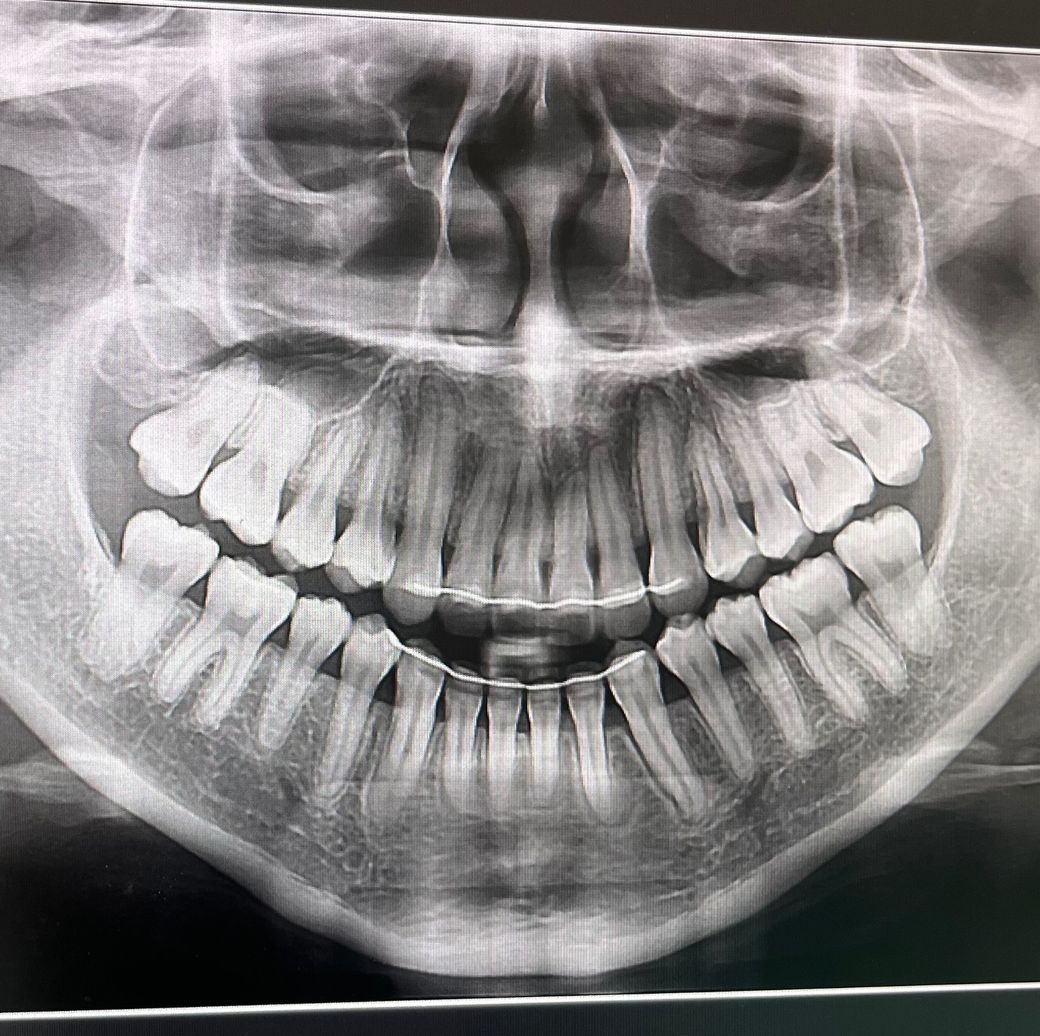

교정 후 혀 내밀기로 인해 브이자 악궁이 되어서 재교정을 생각 중입니다 근데 제가 잇몸톼축도 있고 앞 아랫니가 통증이 살짝 있어서요… 치근흡수가 많이 진행된 걸까요? 재교정은 못하겠죠ㅠㅠㅠㅠㅠ

엑스레이 상으로는 크게 치근이 흡수된건 아닌거 같습니다. 아래 앞니의 경우는 원래 치아 뿌리가 짧기 때문에 관리를 잘하시는게 중요합니다.

아래 앞니의 경우 약간의 치근흡수가 보이지만 많이 흡수된것은 아닌것으로 보입니다. 너무 걱정하지 않으셔도 됩니다.

하지만 재교정 가능여부는 교정치과에서 교정진단을 받아 보는것이 좋습니다.

치근흡수가 심한 정도는 아닙니다. 치과 가보시고 상황에 맞게 재교정도 가능할 것 입니다.

치근흡수는 아주 조금 되었고 전반적인 잇몸뼈 상태도 양호해서 교정하시는데 무리는 없겠습니다.

너무 걱정하지마시고 일단 교정치과에서 상담을 한번 받아보시길 바라겠습니다.

파노라마 엑스레이 사진은 왜곡이 있어 치근흡수에 대한 정확한 판단은 어렵습니다 심하진 않은 것 같습니다